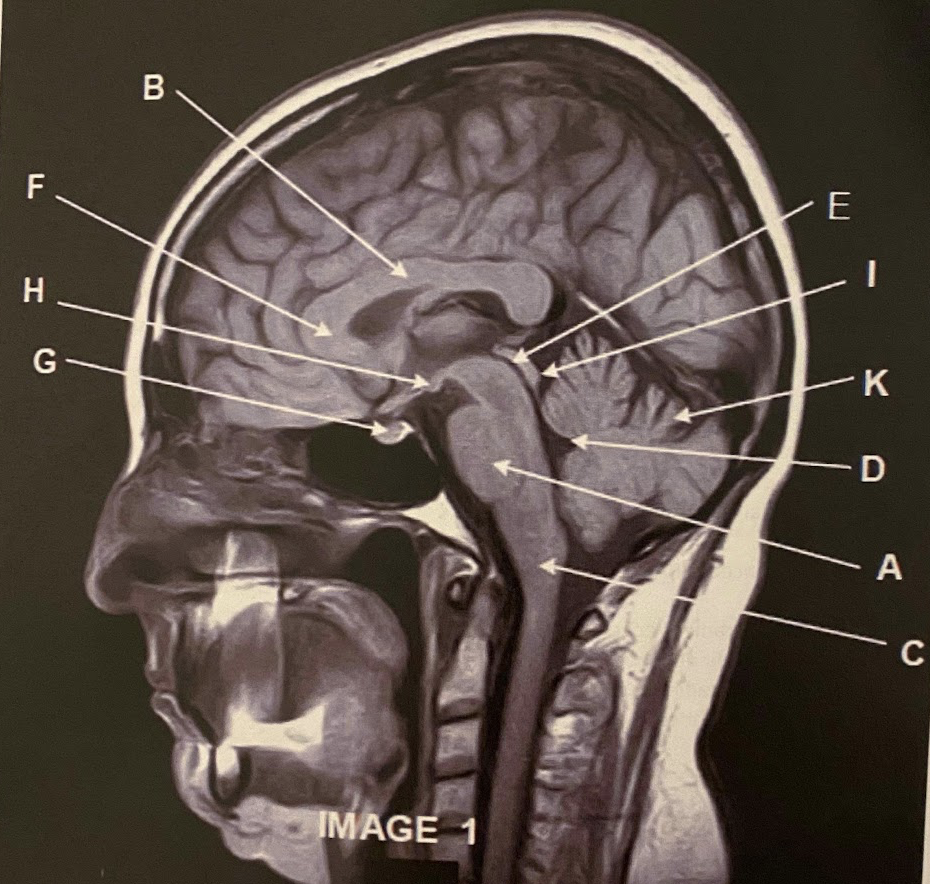

The sagittal scan, demonstrates typical hyper intense tendril-like projections in the corpus callous characteristically seen in patients with what disease?

What anatomy is letter A pointing to?

Pons

What anatomy is letter B pointing to?

Corpus Callosum

What anatomy is letter C pointing to?

A

What anatomy is letter D pointing to?

What anatomy is letter E pointing to?

Aqueduct of Sylvius

Q

Genu of the corpus callous

What anatomy is letter G pointing to?

Pituitary

Mammillary Bodies

What anatomy is letter I pointing to?

Quadrigeminal plate

This image is non-contrasted. It was acquired using a _______ sequence

C) FLAIR

Which letter demonstrates the cervical nerve root exit foramina?

C